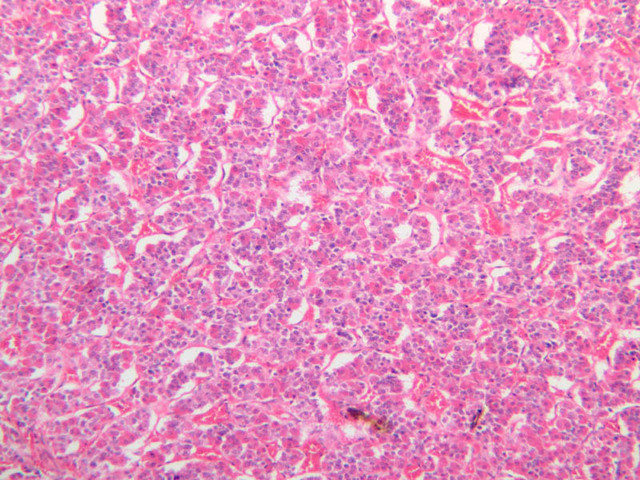

The adrenal gland (slide B-59, H&E [2.5x-labeled, 10x-labeled, 20x, 40x-labeled] [2.5x, 10x-labeled, 20x, 40x]; B-60, H&E [2.5x-labeled, 10x, 20x, 40x]; B-62, H&E [10x, 20x, 40x] [2.5x, 10x]) is a composite organ consisting of two functionally, structurally and embryologically different parts—an outer cortex and an inner medulla. Observe the gland at low power. Find the loosely organized tissue that comprises the medulla and the partially-separated columns of cells that make up the cortex. Scan the capsule and the tissue around it, looking for nerves and blood vessels. Study the pattern of cortical vasculature. In a pattern similar to that seen in the pars distalis of the pituitary, sinusoids run along the edges of columns or cords of cells. Owing to different arrangements of its constituent cells, the adrenal cortex has a layered appearance. From the capsule inward, these cortical layers are known as the zona glomerulosa, the zona fasciculata, and the zona reticularis.

The zona glomerulosa is located immediately beneath the capsule (B-60 adrenal gland, dog [10x, 20x] [20x, 40x]; B-59 [2.5x, 10x, 20x] [2.5x, 10x, 20x]). Its constituent cells are arranged in arcs or spheres, and, owing to their relatively small size, their nuclei appear to be close together. Cells of the zona glomerulosa secrete mineralocorticoids (e.g., aldosterone). The zona fasciculata consists of parallel columns or cords of cells that radiate toward the medulla and are separated by blood sinusoids (B-60 [2.5x, 10x, 20x, 40x]; B-62 [20x, 40x]). Owing to the extraction of lipids during histological processing, the cytoplasm of cells in the zona fasciculata appears highly vacuolated or "foamy". Cells of the zona fasciculata secrete glucocorticoids (e.g., hydrocortisone & cortisone) and some gonadocorticoids (weak androgens). The zona reticularis is the deepest cortical layer and lies adjacent to the medulla (B-60 [20x, 40x]; B-62 [20x, 40x]). It is characterized by irregular, interconnecting cords of cells which are separated by anastomosing capillary networks or sinusoids. Cells of the zona reticularis, which are smaller than those of zona fasciculata and do not contain as many lipid vacuoles, secrete gonadocorticoids and some glucocorticoids.

The medulla is composed of large epithelioid cells, arranged in small groups or cords which are separated by blood vessels. Usually, several large veins mark the center of the medulla. When fresh adrenal gland is incubated in solutions of chromium salts (as was the specimen on slide B-61), brownish precipitates form in the cells of the medulla-- hence, the name chromaffin cell (B-61, chromaffin [2.5x, 10x, 20x, 40x] [2.5x, 10x, 20x, 40x-labeled]). The more darkly stained chromaffin cells are known to contain norepinephrine, the less darkly stained cells, epinephrine. In essence, chromaffin cells are specialized postganglionic sympathetic neurons. How does the ultrastructure of these cells differ from that of the secretory cells of the adrenal cortex?